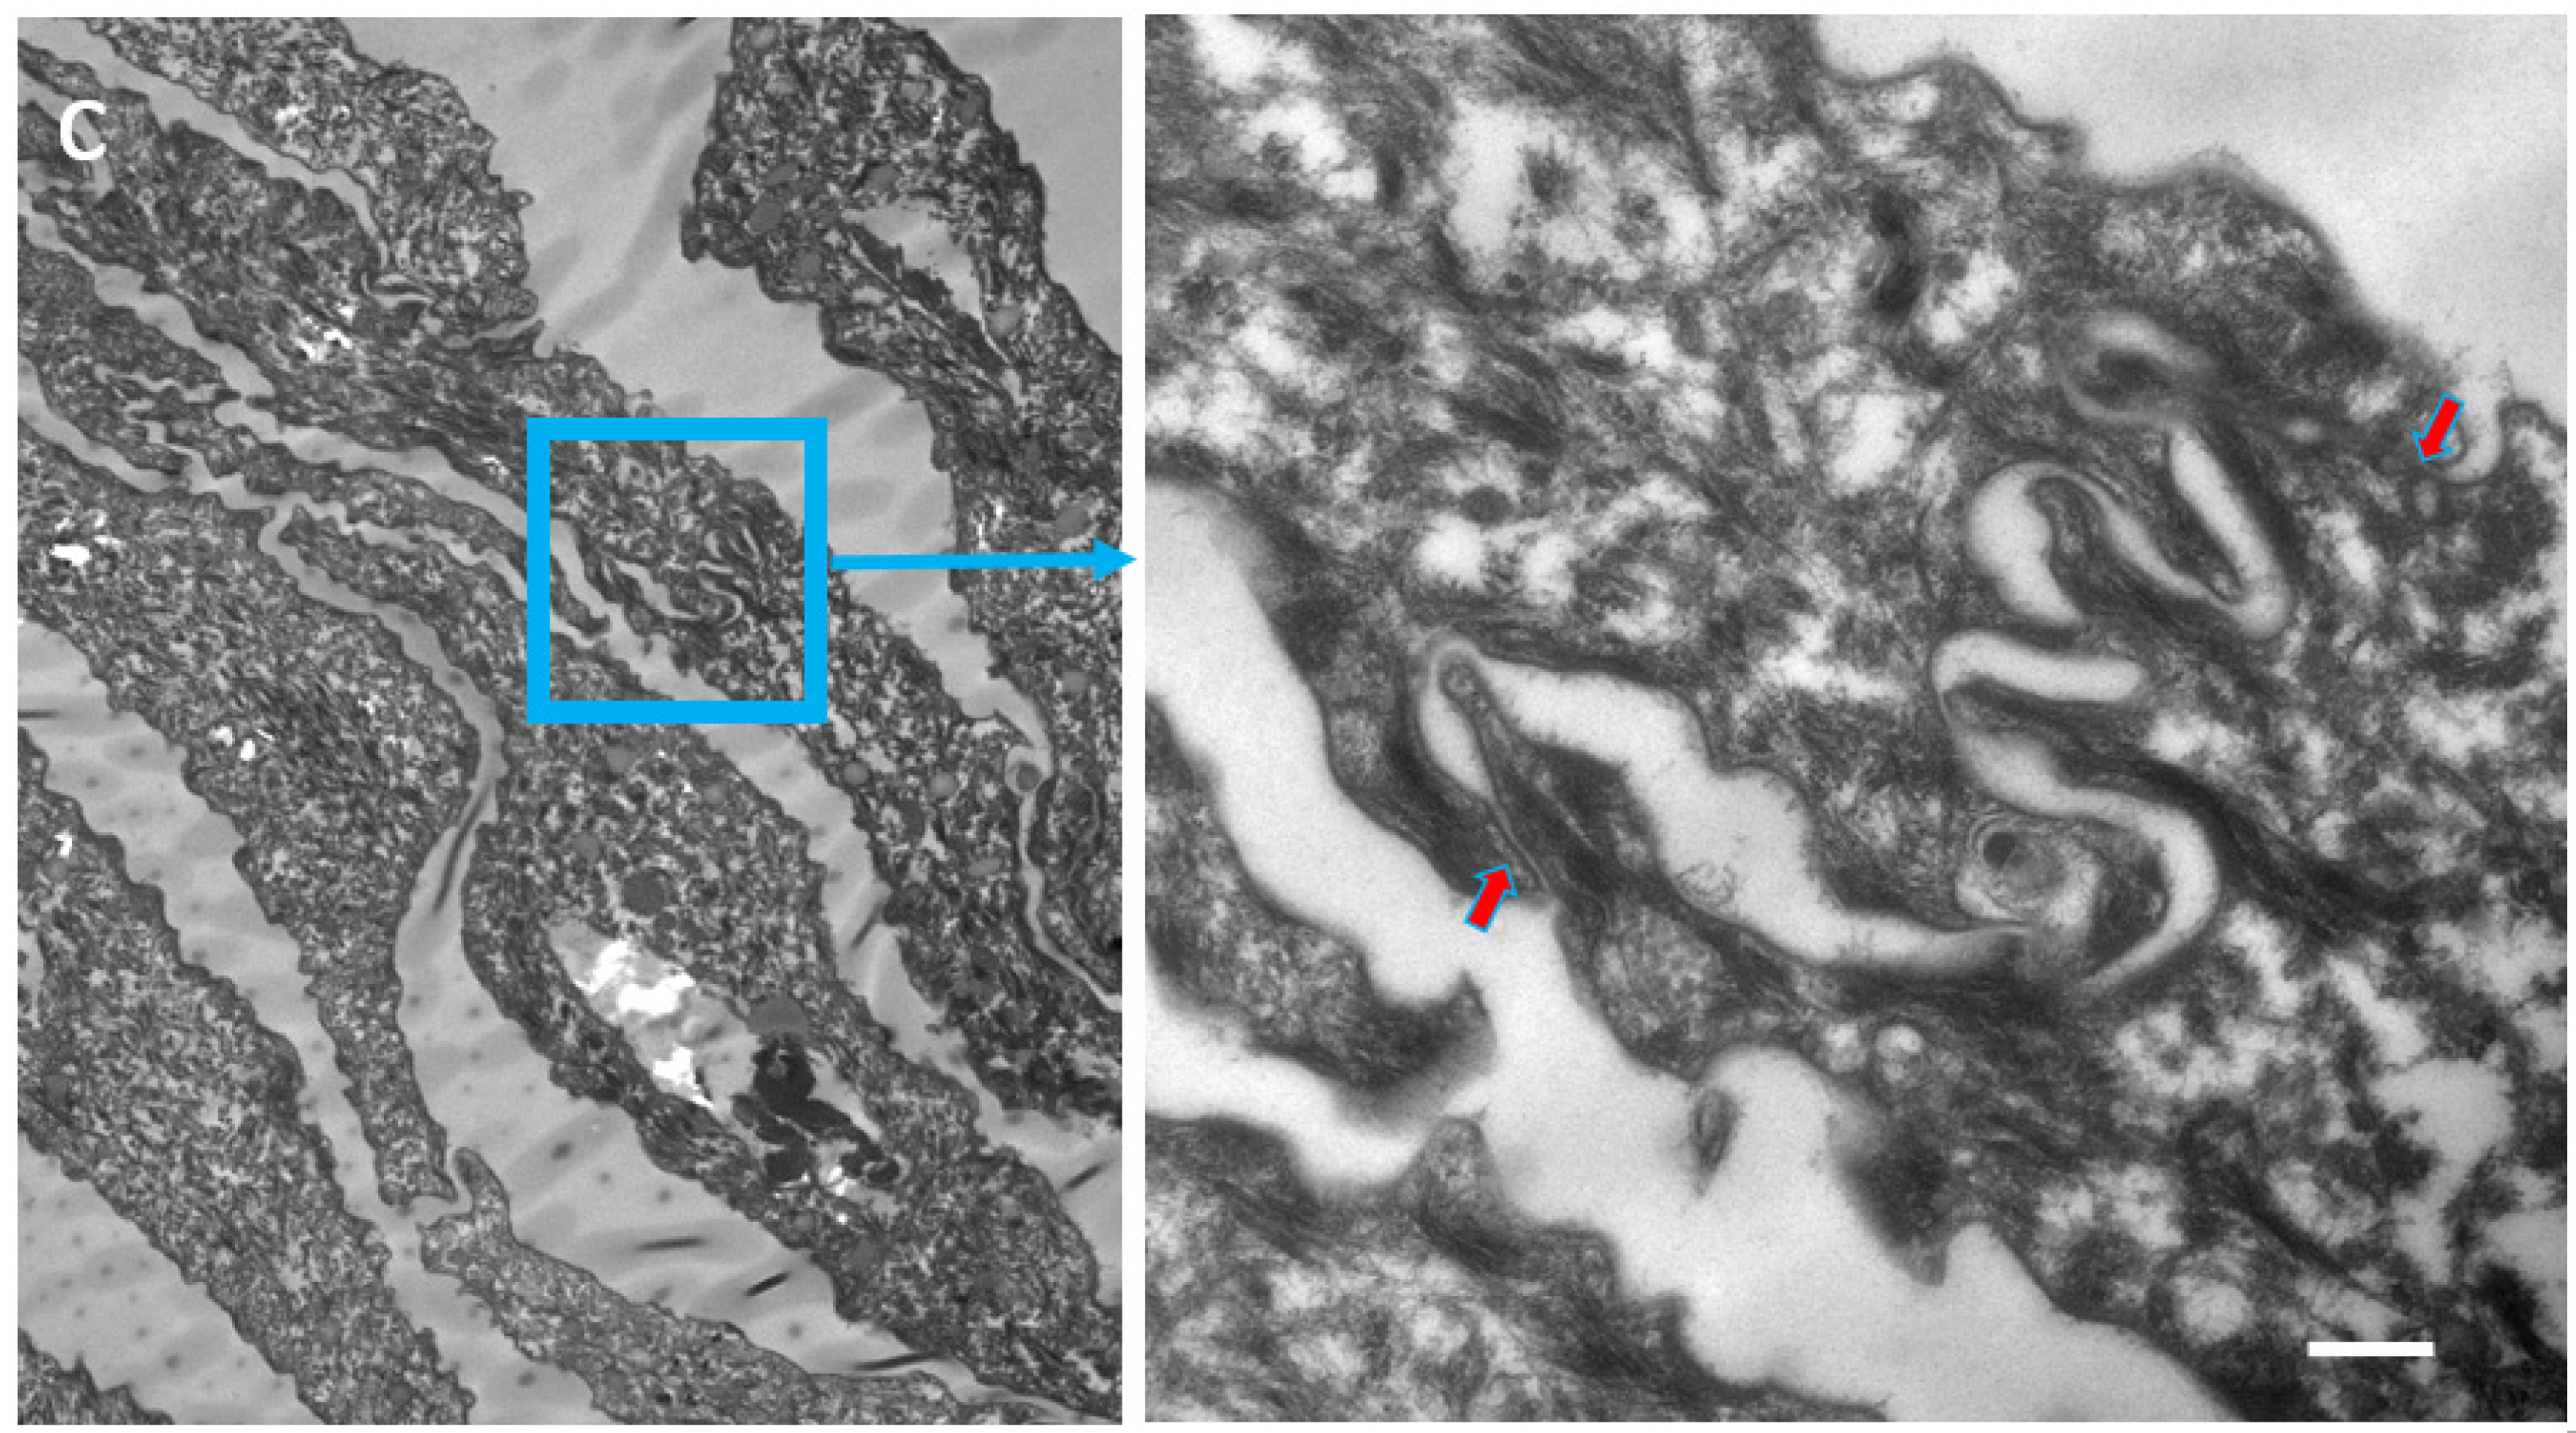

We proposed the hypothesis that in Cldn1 deficient human skin, reactive hyperkeratosis may compensate for defective TJ function. Contrary to the mouse SC which also shows hyperkeratosis in the absence of Cldn1, the horny layer in humans appears to be better fit for providing the barrier function (Figure 2a–c; Table 3).

Figure 2.

Ultrastructural features of SC in patients with IHSC include problems related to lipid extrusion (a), abnormal convolution of cell walls, and increased retention of TJ-derived intercorneocyte rivets (b,c). TJ-derived fusion points between the lateral walls of cornified cells persist up to the surface of hyperkeratotic SC, shown in (c), where corneodesmosomes are no longer present. Arrows point to TJ remnants isolating the extracellular space between adjacent uppermost corneocytes. In (c), the right panel shows a high power view of the SC disjunctum area delimited by the rectangle to the left. d = (corneo)desmosome; red arrows = TJ-derived structure. Bars = 200 nm.

Table 3.

Increased presence of fused TJ remnants in the SC of IHSC. TJ-derived fusions within the apical-lateral contacts of corneocytes were counted in the first four layers of SC. At least 100 apical-lateral contacts were examined at high magnification on several ultrafine sections of each specimen. NHS = normal human skin.

Two patients with IHSC syndrome were examined: one bearing a homozygous deletion (200delTT) in the first exon of the CLDN1 gene, resulting in a premature stop codon [37], the other a CLDN1 frameshift mutation in exon 2 [38]. Both showed a total absence of the protein. Morphological examination of IHSC biopsies revealed acanthosis, focal parakeratosis, and papillomatosis characteristic of an epidermal proliferative response. Partial retention of lamellar granules and numerous lipid vacuoles in the SC could be seen ultrastructurally. Highly convoluted lateral walls of corneocytes with narrow intercellular spaces and numerous TJ-derived contacts persisted throughout the thickened SC.